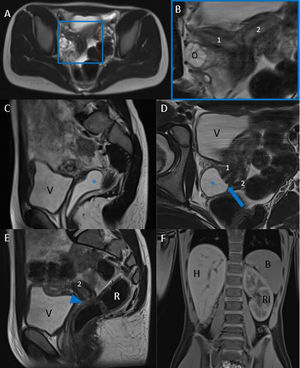

Ecografías abdominopélvicas. A) Riñón izquierdo único, compensador (cabezas de flecha, delimitando sus bordes). B) Colección líquida paravesical de 48 x 18mm con ecos finos internos (flecha). C y D) Malformación uterina con aparente útero bicorne bicollis con ambos cuerpos uterinos en anteflexión (1. derecho: 27mm / 2. izquierdo: 24mm), cada uno lateralizado hacia un lado, con colección adyacente a útero derecho (flecha). Ambos endometrios centrados.

Presentación del casoPresentamos el caso de una niña prepuberal de 10 años en seguimiento pediátrico que fue diagnosticada prenatalmente de riñón izquierdo único. Durante el seguimiento ecográfico posnatal, se detectó una estructura tubular con contenido líquido-anecoico en la pelvis, con estrechamiento hacia la uretra derecha, planteando inicialmente un diagnóstico diferencial entre resto mesonéfrico/uracal atípico, riñón derecho ectópico y atrófico. Se repitió la ecografía posteriormente (fig. 1.), en la que se identificó la presencia de un útero bicorne bicollis con colección líquida cerca de la vagina. La resonancia magnética (RM) confirmó un útero didelfo con hemivagina derecha ciega y hemivagina izquierda permeable (fig. 2). Se realizó vaginoscopia para confirmar la permeabilidad de la hemivagina izquierda y, actualmente, está en lista de espera para tratamiento definitivo con vaginoplastia.